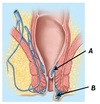

Name structures A and B

A - Falciform ligament

B - Greater omentum

Name structure A

A - Lesser omentum